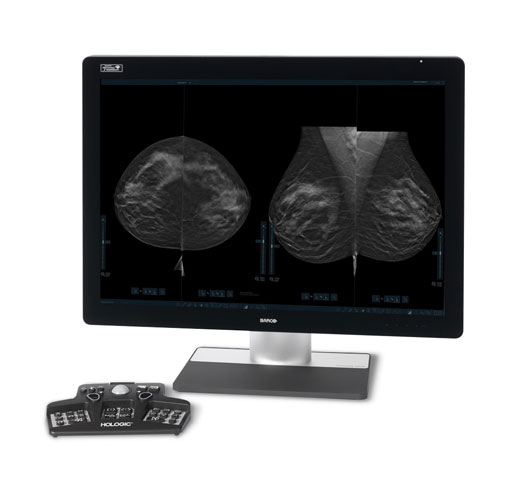

Breast Health

Hologic is transforming breast care. We apply cutting-edge science to accelerate discovery, improve efficiency and continually sharpen precision.

Breast Health Continuum of Care

Time is precious when it comes to effective detection, diagnosis and treatment of breast cancer. We strive to save you time at every step along the Breast Health Continuum of Care to help more women have more time in better health.